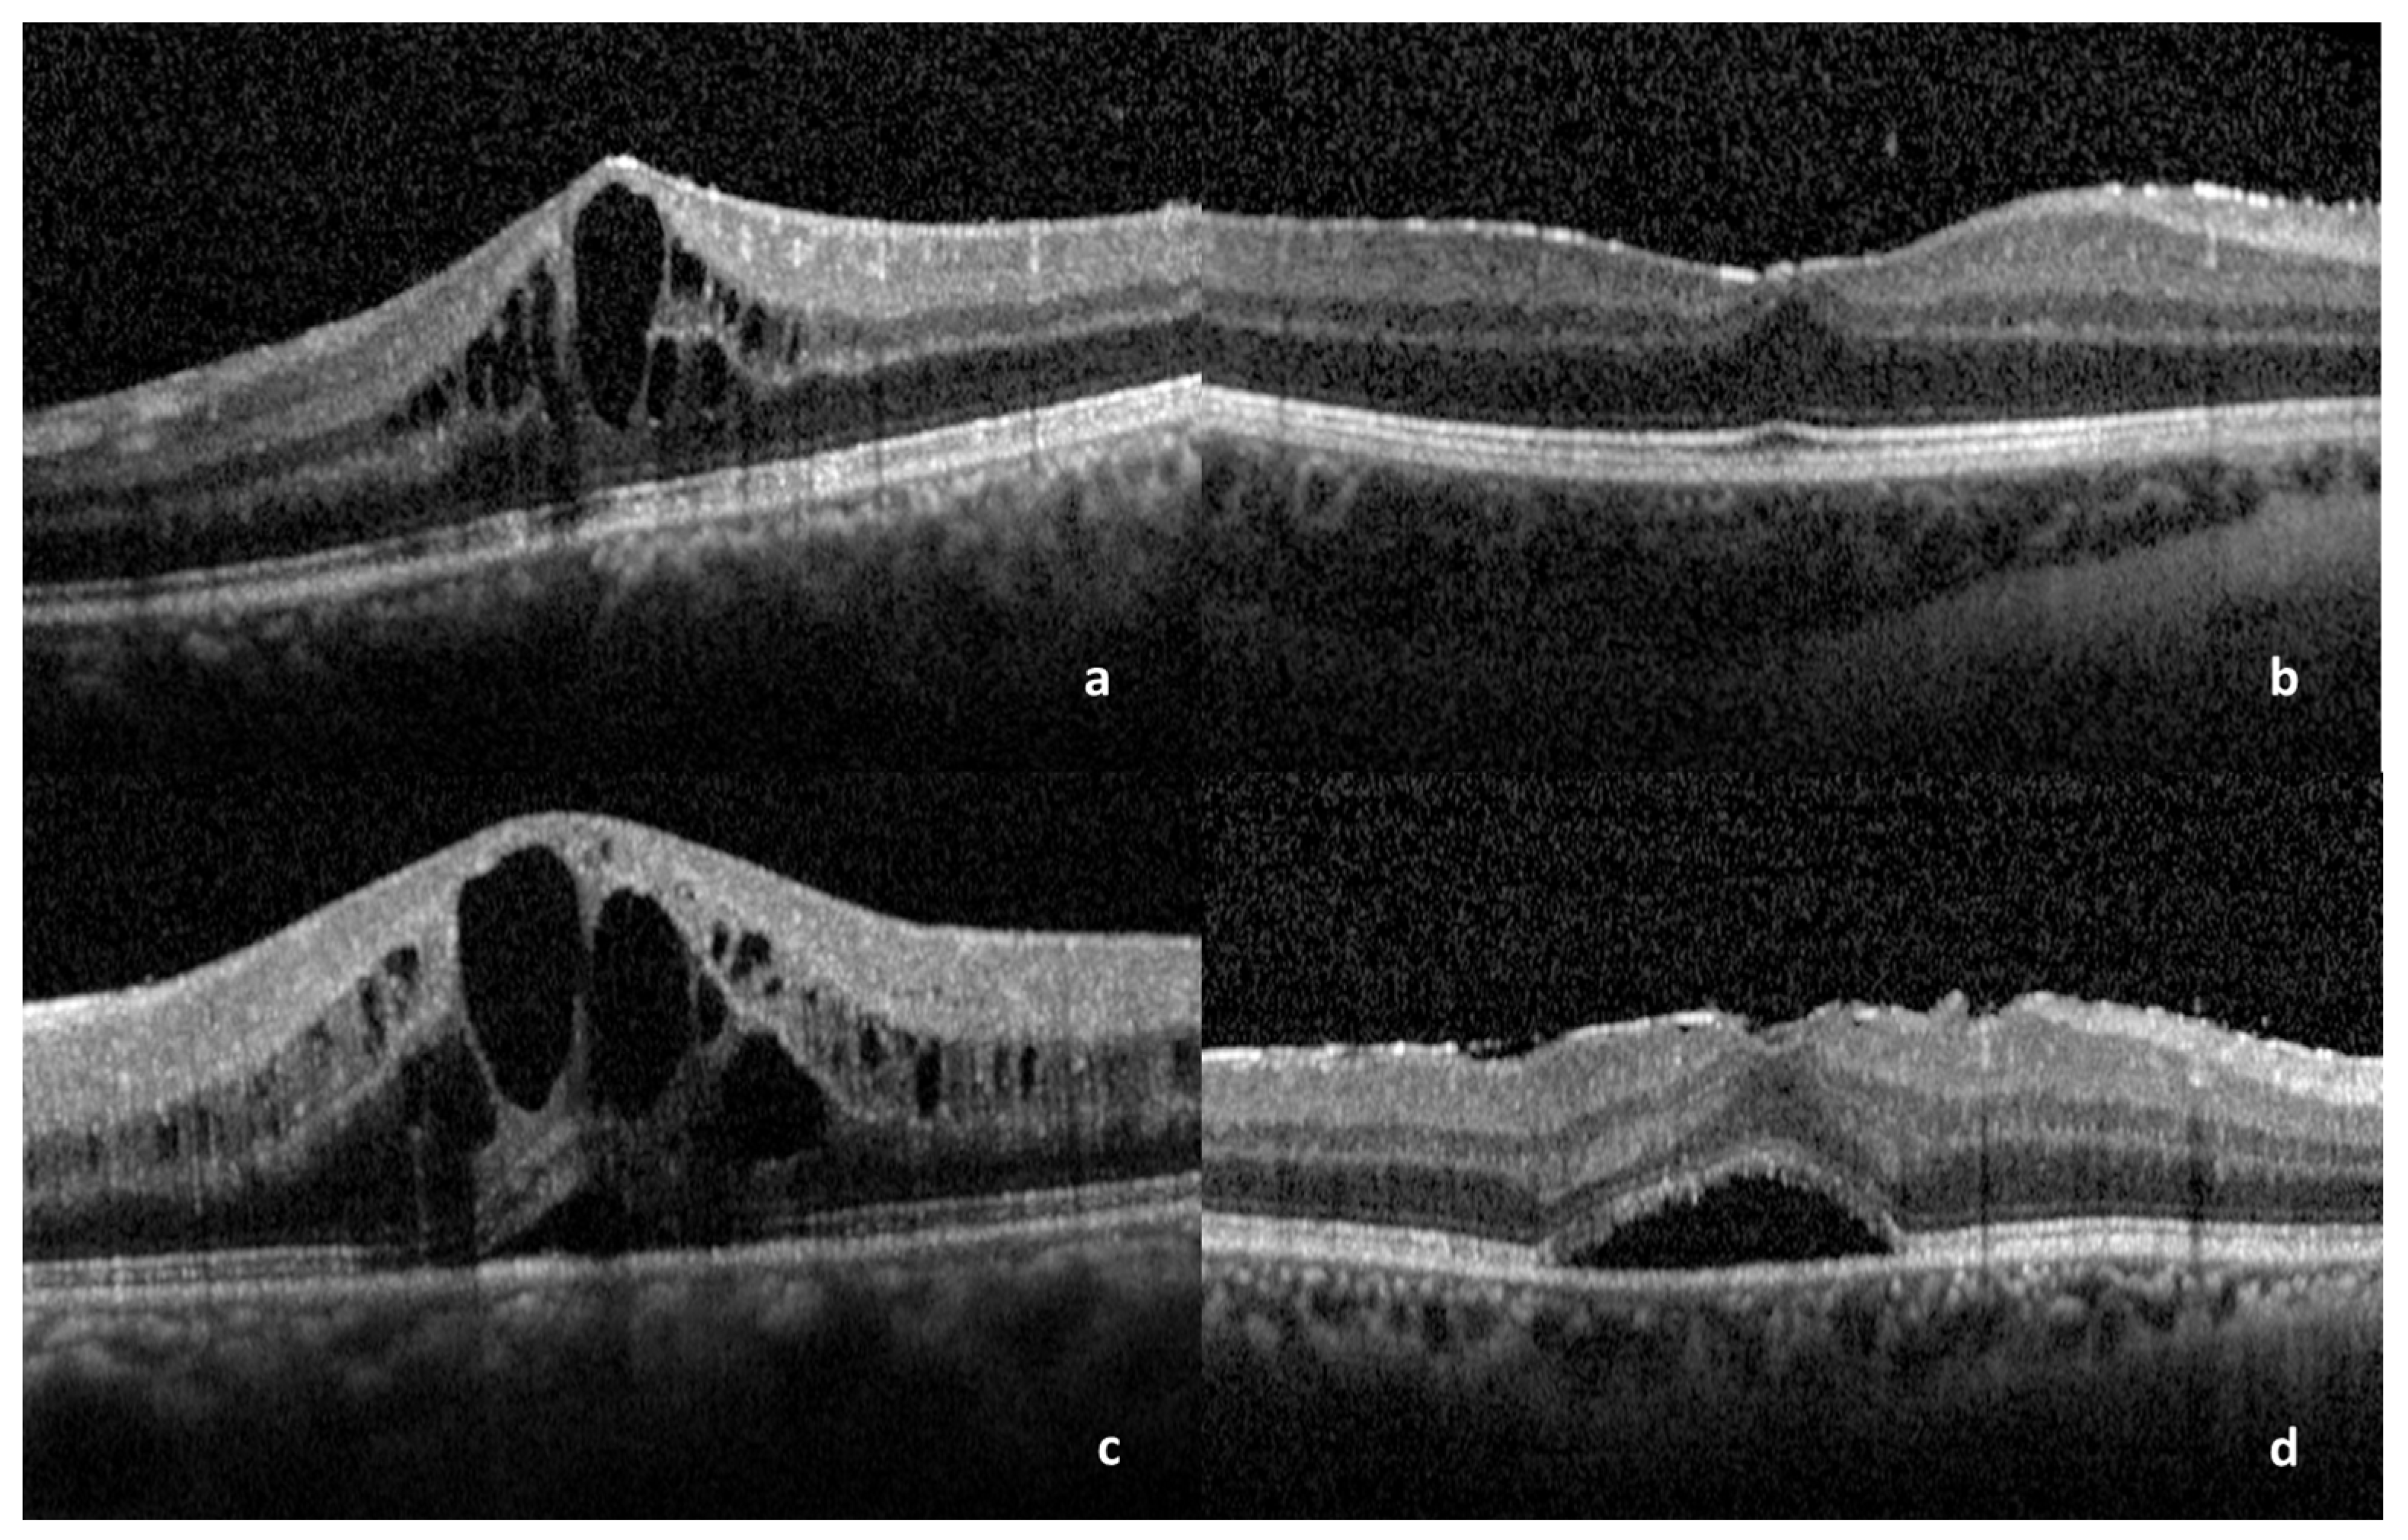

| Number of Eyes (%) | Median BCVA (1st–3rd Quartile) | |

|---|---|---|

| Total | 27 | 0.8 (0.55–0.95) |

| DME | 9 (33.3%) | 0.8 (0.45–0.975) |

| CME | 18 (66.6%) | 0.9 (0.7–0.9) |

| SRD * | 13 (48.1%) | 0.7 (0.4–0.8) |

| Subfoveal bubble * | 12 (44.4%) | 0.8 (0.375–0.9) |

| Foveal Bulge * | 11 (40.7%) | 0.9 (0.8–0.95) |

| EZ disruption * | 3 (11.1%) | 0.6 (0.45–0.75) |

| ELM disruption * | 0 (0%) | |

| COST line disruption * | 6 (22.2%) | 0.9 (0.675–0.9) |

| ERM * | 17 (62%) | 0.8 (0.6–1.0) |

| Central subfield thickness | 459 (±153) | |

| Central perifoveal thickness | 443 (±189) |